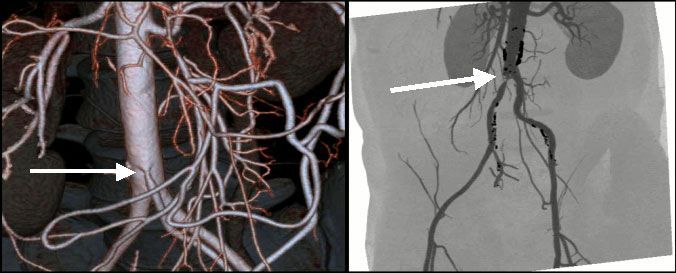

IV. Периферические артерии верхних и нижних конечностей.

Клиника поражения периферических артерий, особенно при сахарном диабете, осложненном диабетической ангиопатией – это показание для направления на МСКТ. Следующая группа пациентов - это курильщики со стажем. Доказано прямое повреждение эндотелия сосудистой стенки при курении табака, поэтому частота облитерирующих заболеваний артерий у таких больных значительно выше. Результаты исследования помогут врачу в выборе проводимой терапии, в том числе малоинвазивного эндохирургического способа лечения.

![]() |

| Рис.15-16. 3-D реконструкция периферических артерий при МСКТ. Окклюзия левой подколенной артерии (стрелка). Множественные атеросклеротические поражения, правой бедренной и правой подколенной артерии. |